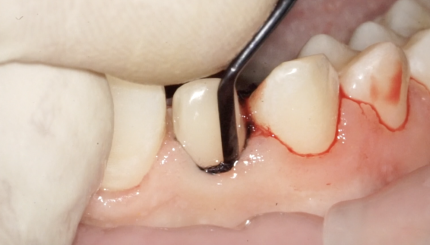

43 42 41 31 32 Финишное препарирование + ретракция

10 августа 2021